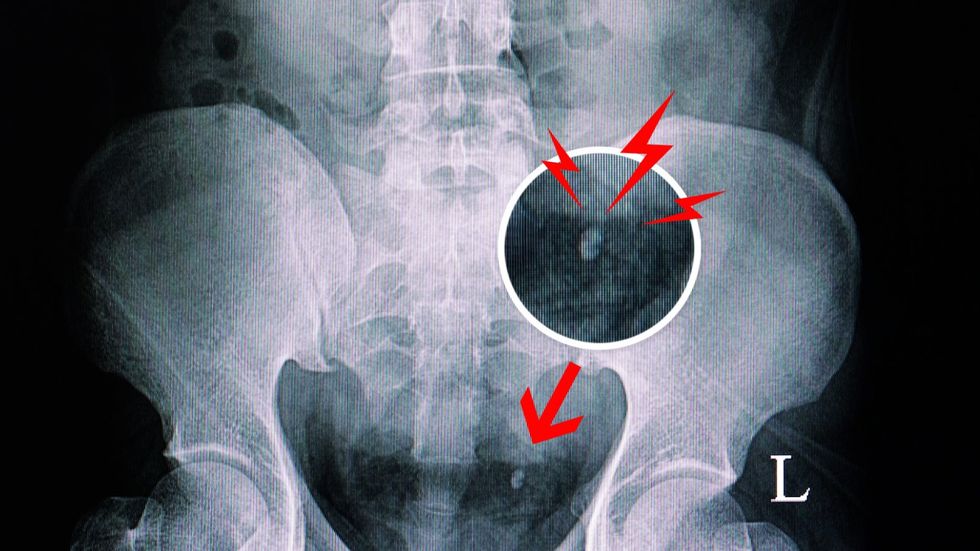

Gurët në veshka (nefrolitiaza) janë depozita të forta mineralesh dhe kripërash që formohen në veshka. Mjekët thonë se kjo sëmundje në një masë të madhe është pasojë e zakoneve jo të shëndetshme të jetesës, sidomos e marrjes së pamjaftueshme të ujit. Vërehet se pacientët me gurë në veshka shpesh harrojnë të pinë ujë gjatë ditës. Megjithatë, jo të gjithë faktorët e rrezikut mund të kontrollohen plotësisht, sepse nefrolitiaza lidhet edhe me predispozicionin gjenetik ose me disa gjendje shëndetësore. Kur flitet për faktorët që mund të kontrollohen, ekspertët theksojnë para së gjithash marrjen e mjaftueshme të ujit, por edhe stresin e përditshëm, i cili mund të ndikojë gradualisht në shumë pjesë të trupit, përfshirë edhe veshkat.

Gurët në veshka ose në rrugët urinare janë pasojë e zvogëlimit të vëllimit të urinës dhe grumbullimit të kalciumit dhe substancave të tjera që formojnë gurin. Dehidratimi, pra marrja e pamjaftueshme e lëngjeve, është faktori më i shpeshtë i rrezikut për krijimin e gurëve në veshka.

Dr. Sangeetha Murugapandian, specialiste për sëmundjet e veshkave, thotë se gurët në veshka mund të jenë edhe sa një “kokërr rëre”, dhe në atë rast kalojnë përmes sistemit urinar pa shkaktuar probleme. Megjithatë, shpesh gurët janë mjaft të mëdhenj për të bllokuar rrugët urinare dhe për të shkaktuar dhimbje shumë të forta në shpinë ose në njërën anë të trupit, gjak në urinë, urinim të shpeshtë dhe të përziera, transmeton Telegrafi.

Është e rëndësishme që gurët në veshka të zbulohen në kohë për të shmangur komplikime si bllokimi i rrjedhjes së urinës (hidronefroza), infeksionet serioze të rrugëve urinare dhe dëmtimi i indit të veshkave.